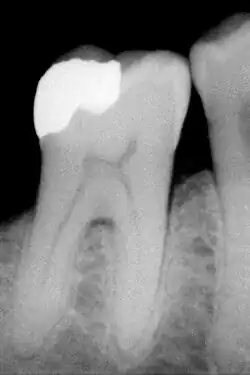

No caso da amálgama de prata utilizada pelo cirurgião-dentista (médico-dentista em Portugal), trata-se de uma liga que contém prata, mercúrio e estanho, podendo haver também o zinco e o cobre. Ela visa restaurar a cavidade causada pela doença cárie e pela manobra operatória do dentista ao remover tecido contaminado.

O amálgama é um material restaurador bastante utilizado pelos dentistas na atualidade[1] em razão de seu baixo custo, facilidade técnica, resistência ao desgaste e selamento marginal; entretanto, pela presença do mercúrio e outros metais pesados - potencialmente tóxicos para o profissional e o paciente, existe uma crescente resistência ao seu uso. Aliado a isso, sendo uma liga metálica, ela é antiestética e está sujeita a corrosão, implicando em pigmentação indesejável da estrutura dentária. Outro fator de restrição é a necessidade de confecção de cavidades retentivas para a pasta, pois não existe adesão do amálgama ao dente, causando assim desgastes excessivos em estruturas que poderiam ser poupadas. Atualmente em alguns países o amálgama está proibido, e onde ainda o usam têm-se buscado substituir o mercúrio pelo gálio[1].